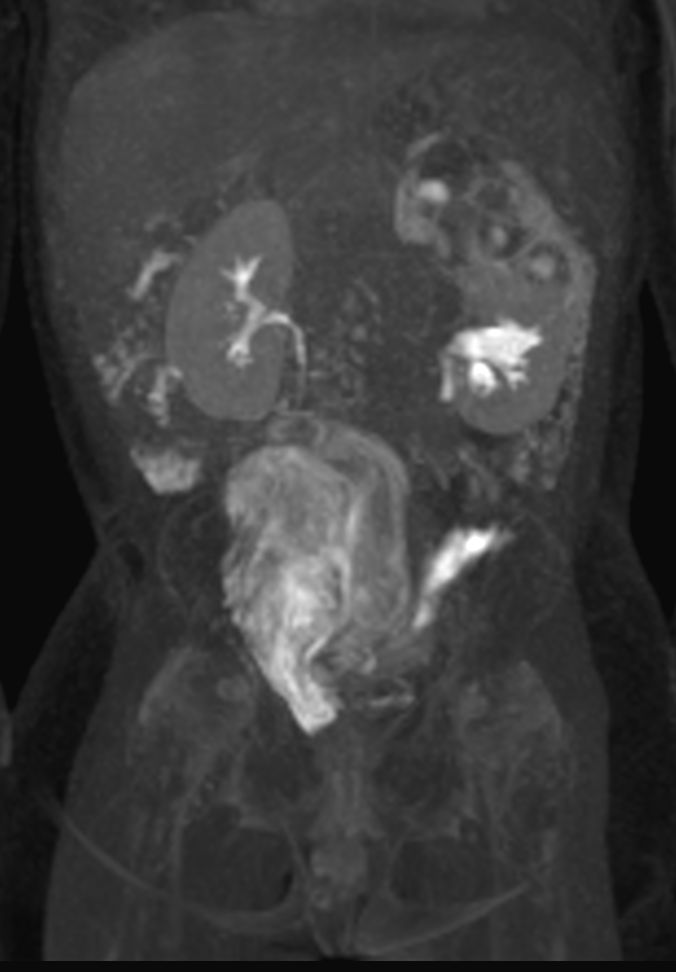

Coronal T2w MultiVane XD